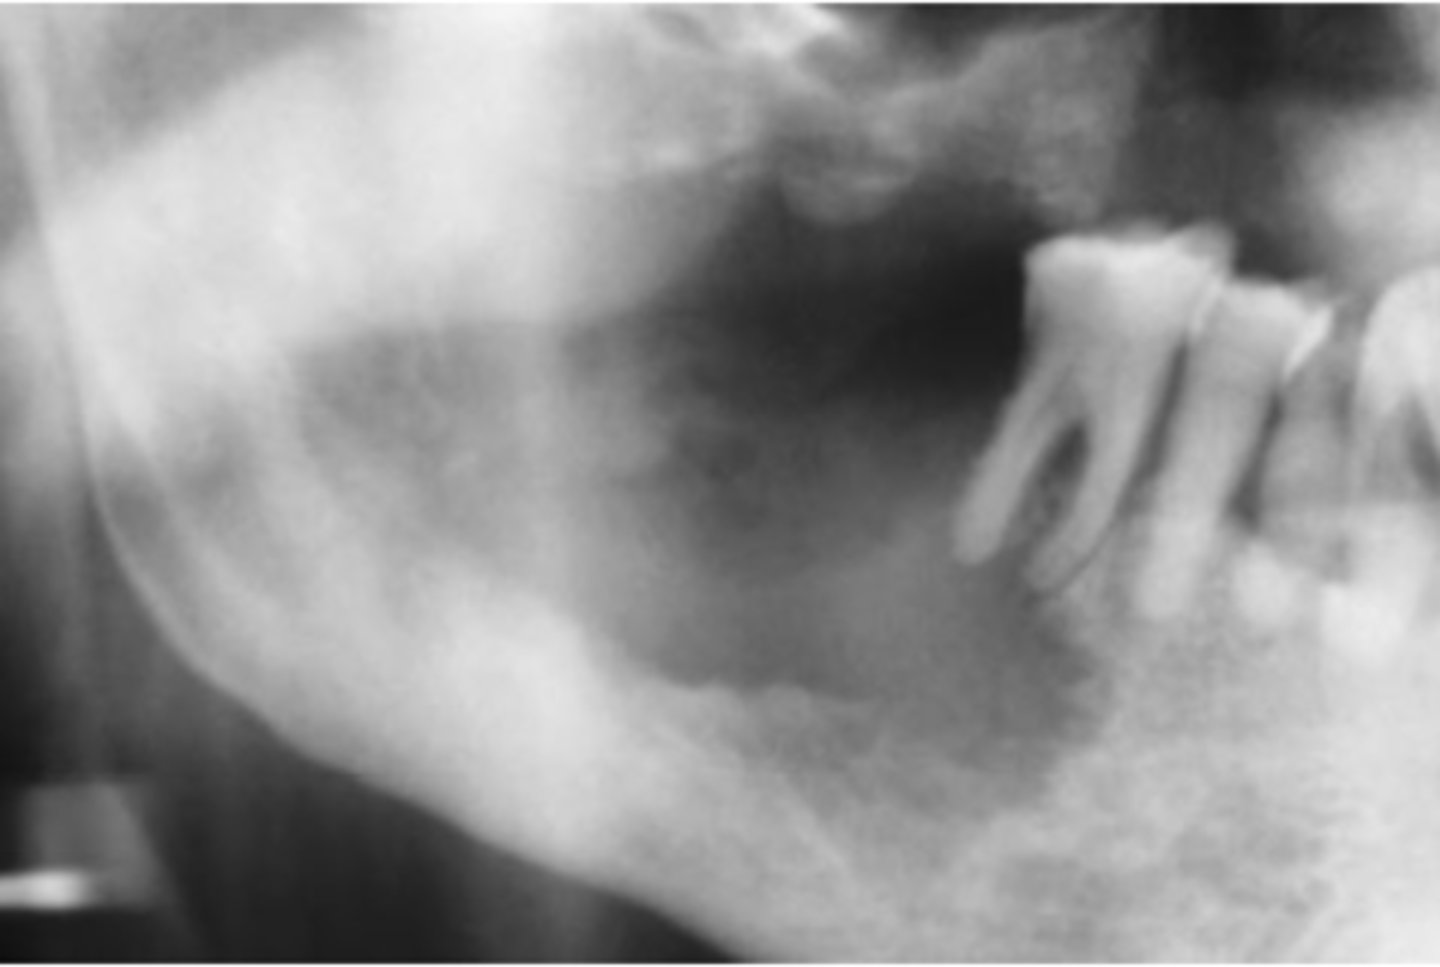

Squamous Cell Carcinoma (gingival and alveolar)

Hint: mimics common, benign inflammatory and reactive lesions (pyogenic granuloma)